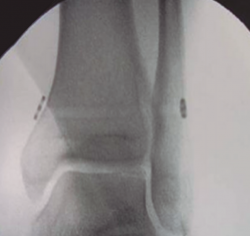

Para evitar problemas asociados con los tornillos, se crean los métodos de fijación elásticos, siendo una buena alternativa desde finales de la década de 1990. Son técnicas más fisiológicas y se adaptan mejor a la dinámica de la sindesmosis. Algunos estudios biomecánicos han descrito que aportan menos reducción que los tornillos y, por tanto, es aconsejable darle tensión al sistema con el tobillo en flexión plantar parcial, permitiendo un mayor ajuste y cierre de la mortaja. La posición del implante es la misma que para los tornillos. Se permite la carga completa a las 2 o 3 semanas. Hasta la fecha, para lesiones aisladas de las sindesmosis inestables, ningún estudio ha demostrado que las técnicas de fijación dinámicas sean inferiores a la fijación rígida con respecto a la estabilidad y la satisfacción del paciente. Los beneficios más notables de esta técnica son evitar un segundo procedimiento quirúrgico para la extracción de los tornillos, la carga más precoz y una menor alteración biomecánica (Figura 4).

figura4.png

Figura 4. Fijación dinámica con botón de sutura.